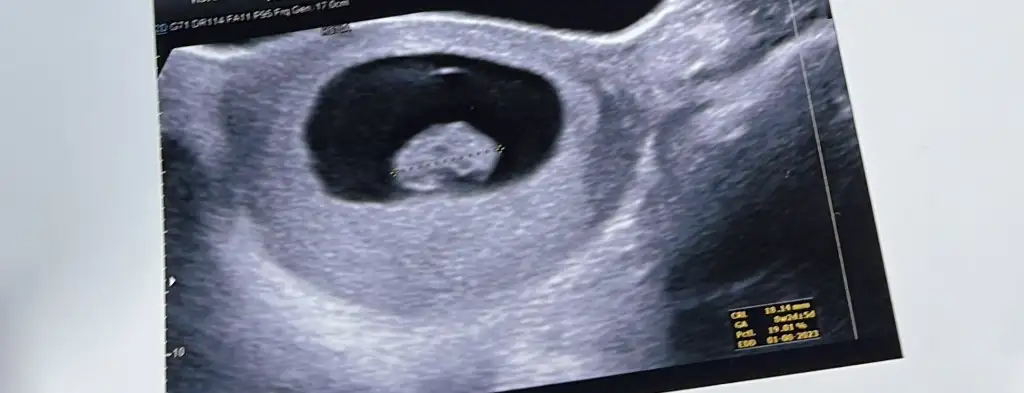

İkili testte 3. De ense ölçümü zor aldılar hareketli pozisyon vermedi 13. Haftada bir doktora gittim göstermedi sabahsi başka bir doktor bacak arasını gösterdi erkek büyük ihtimalle dedi dün 13 haftadaki ilk doktora gittim bacak arasından kordon geciyor cinsiyet görünmüyor cinsiyeti örtmüş tahminde bulunamam dedi bende bu defa acaba diğer doktorun gördüğü kordon muydu kordonu pipi mi zannetti diyorum çünkü bir tek o tahminde bulundu

Attığınız görüntülerde ben asla pipiye benzer bişey göremedim, doktorun baktığı açı tabikide daha iyi onlar canlı canlı bakıyor. Bi 2 hafta daha bekleyin bakalım, gitmeden önce kontrole de biraz yürüyüş yapın su için bol bol görünür belki ❤️

Çok tutarlı diyemem ama ben hamileyken arkadaşlarla hep dikkat etmiştik kız bebeğin başı sağda erkek bebeğin başı solda oluyodu ultrason fotosunda varsayım yani☺️7-8 haftalık fotosu varsa daha net söyleyebilirim ama

Burada 9 haftalık